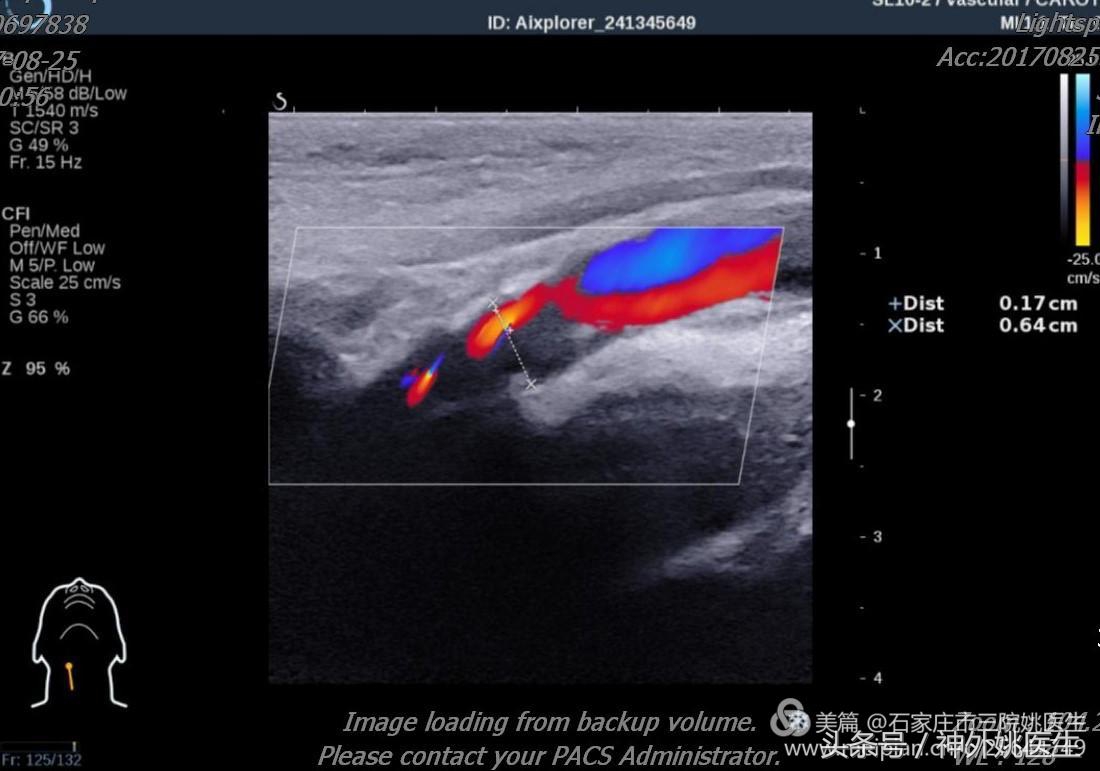

4.颈动脉彩超: 右侧颈内动脉起始部斑块,管腔重度狭窄(70%-99%)(图4、图5)。

图4

图5